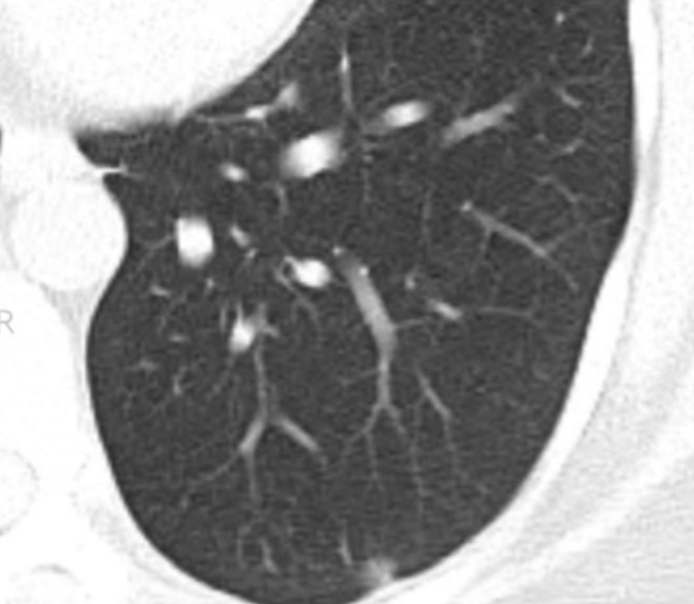

影像病理联合读片之肺原位腺癌

图片尺寸1080x810